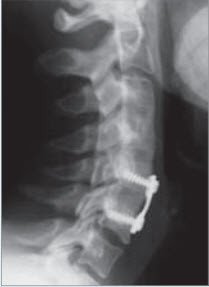

Da die entfernte Bandscheibe einen «Hohlraum» zurücklässt, wird dieser mit einem Platzhalter ausgefüllt. Dies kann mit eigenem Knochen (Beckenkamm) oder mit Fremdmaterial (sog. Cage) erfolgen. Damit erreicht man gleichzeitig eine Verblockung der Wirbelkörper, die mit einer Platte gesichert werden kann. Diese Versteifung beeinträchtigt die Gesamtbeweglichkeit der Halswirbelsäule kaum. Gelegentlich wird anstelle der Verblockung die Bandscheibe durch eine bewegliche Prothese ersetzt.

Gegen Verkrampfungen der Genick- und Schultermuskulatur helfen warme Duschen und Bäder, warme Heublumen-Packungen oder auch die einfache warme Bettflasche. Die Schonungszeit beträgt sechs Wochen. Schmerzmittel sind meist nach wenigen Tagen nur noch selten oder sporadisch notwendig. Nach Versteifung ist die Behandlung die gleiche wie jene ohne Versteifung. Die Knochen-Entnahmestelle am Beckenkamm kann für einige Tage zum Gebrauch einfacher Schmerzmittel zwingen. Rund sechs Wochen nach der Operation wird die Kontrolle mit einfachen Röntgenbildern der Halswirbelsäule durchgeführt.